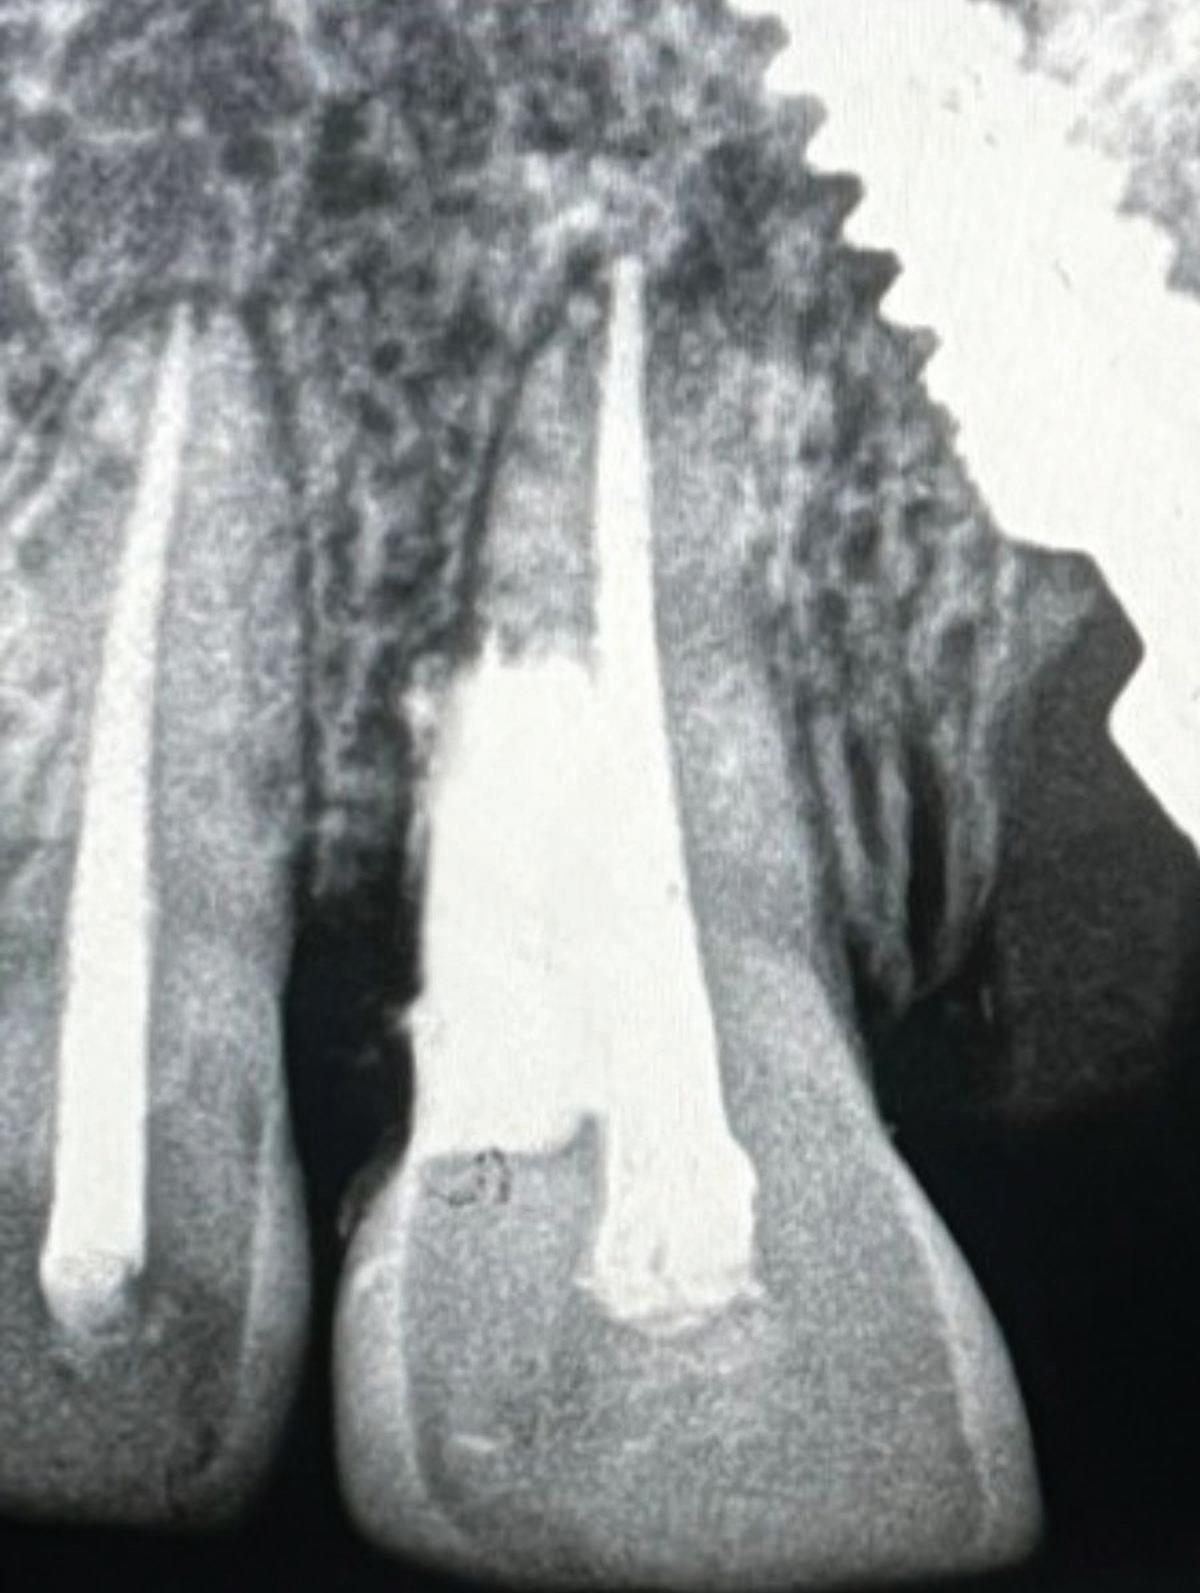

In the endodontic stage, conservative endodontic preparation and obturation with modern techniques are performed as they are for any tooth. All endodontic procedures are performed under an operating microscope to maximize visualization and illumination of the fracture line (Fig 1). The coronal portion of the newly placed gutta percha is removed 2 to 3 mm below the deepest extent of the crack in the affected canal to prepare for intraradicular barrier placement (Fig 2). Gutta percha is also removed 2 to 3 mm into the other noncracked canal orifices in the tooth to prepare for traditional orifice barriers. Microscopic transillumination with a fiber-optic light, in which an LED light probe is placed against buccal or lingual tissues overlying the roots, is utilized to illuminate the root and enhance visualization of the crack (Fig 3). A flowable resin-modified glassionomer or composite resin is then placed in this newly created void from the level of the gutta percha to the floor of the pulp chamber in all canal orifices (Fig 4). A composite resin core is then placed to permanently restore the endodontic access. If a temporary or permanent crown is not placed immediately after the endodontic procedures, the tooth is reduced

Periapical radiograph at the completion of the endodontic protocol. Resin-modified glass ionomer cement is placed as an intraradicular barrier in the distal canal, along the pulpal floor, and as an orifice barrier in the mesial canals.

completely out of occlusion, eliminating all functional and excursive contacts. The patient is instructed to chew exclusively on the contralateral side.

The placement of intraradicular barriers in the described protocol is based on empirical data supporting their efficacy in improving both the seal and fracture resistance at the pericervical dentin. Studies on canal orifice barriers have noted that a minimum of 2 to 3 mm of material is necessary to create a coronal seal.28,29 In this protocol, removal of gutta percha to this depth was chosen to maximize the seal below the level of the crack on intact dentin. Studies have also shown that placement of these barriers can enhance the pericervical dentin’s

Fig 1. Microscopic visualization of the radicular extension of the crack (arrows) entering the canal.

Fig 4.

Fig 2. Gutta percha removed 2 mm apical to the terminus of the fracture (arrows).

resistance to fracture.30-32 Therefore, the recommendation in the protocol of placing these deep intracanal restorations maximizes both the seal internally and the fracture resistance of the root. A composite or glass ionomer core is placed after the intraradicular and orifice barriers to restore the endodontic access cavity and complete the internal seal of the crack. Posts should be avoided in cracked teeth as they decrease fracture resistance of pericervical dentin and have been linked to lower survival rates.15,27,33